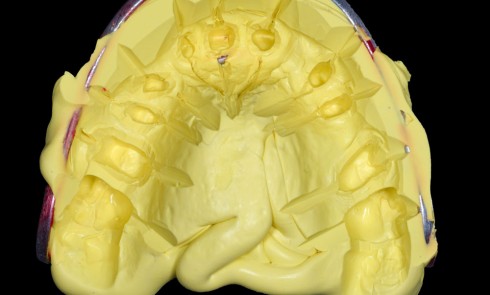

– obtention d’une étanchéité coronaire efficace le plus rapidement possible par le scellement d’un inlay-core et d’une couronne provisoire si les tissus dentaires résiduels sont insuffisants (fig. 1).

L’étanchéité des obturations coronaires provisoires et permanentes conditionne pour une grande part la réussite du traitement endodontique. Ainsi, en 1987, Swanson et Madison [42] ont montré qu’un traitement endodontique parfaitement réalisé était infiltré par des bactéries sur près de 85 % de sa hauteur entre 3 et 56 jours en l’absence de fermeture de la cavité d’accès endodontique. De la même manière, Torabinejad et coll. [44] ont étudié la pénétration de deux espèces bactériennes (Staphylococcus epidermis et Proteus vulgaris) au sein de canaux obturés par une technique de condensation latérale. Ils ont montré que dans plus de 50 % des canaux traités, les bactéries étaient retrouvées au niveau de l’apex 19 jours seulement après exposition à Staphylococcus epidermis et 42 jours après exposition de la cavité d’accès à Proteus vulgaris. Khayat et coll., en 1993 [12], ont montré qu’après 30 jours d’exposition à la salive naturelle, des bactéries étaient retrouvées au niveau apical pour l’ensemble des canaux traités.

En 1995, Ray et Trope [22] ont évalué radiographiquement sur près de 1 000 dents l’apparition ou non de lésions apicales selon les qualités de la restauration coronaire et de l’obturation canalaire. Les auteurs ont montré qu’un traitement endodontique de mauvaise qualité associé à une restauration coronaire de qualité donne de meilleurs résultats en termes de non-survenue d’une LIPOE qu’un traitement endodontique bien mené associé à une obturation coronaire défectueuse. Tavares et coll., en 2009 [43], confirment cette étude, en montrant que le taux de succès du traitement endodontique est plus élevé lorsque la restauration coronaire est de bonne qualité, et ce, indépendamment de la qualité du traitement endodontique.

Toutefois, la qualité d’une obturation coronaire, aussi bonne soit-elle, ne peut en aucun cas compenser un traitement endodontique de mauvaise qualité [45].